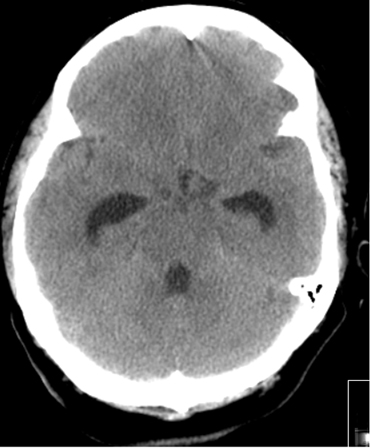

A hidrocefalia aguda ocorre em 15% a 20% dos pacientes durante as primeiras 72 horas e é uma hidrocefalia obstrutiva.[11][12][180] Sua ocorrência está relacionada à presença de sangue intraventricular e, em menor extensão, a um acúmulo grosso de sangue na cisterna.[180][181] A taxa de mortalidade em pacientes de HSA com hidrocefalia é maior que naqueles sem hidrocefalia.[180]

Em pacientes com HSAa e hidrocefalia sintomática aguda, deve ser realizada a derivação urgente do líquido cefalorraquidiano (LCR) (drenagem ventricular externa [DVE] e/ou drenagem lombar).[37] O uso de antibióticos profiláticos com a DVE não está estabelecido, mas é comumente adotado.[60] Os modos ideais de drenagem do LCR (intermitente vs contínuo), desmame do DVE (rápido vs gradual) e o momento do desmame do DVE (após a estabilização do aneurisma vs momento de risco de vasoespasmo) são incertos.[7][113][182] Não está claro se a fenestração microcirúrgica da lâmina terminal durante a clipagem cirúrgica do aneurisma protege contra a necessidade de um shunt permanente em pacientes com hidrocefalia.[183][Figure caption and citation for the preceding image starts]: Hidrocefalia comunicante no cenário de hemorragia subaracnoide; observe a dilatação do quarto corno e do corno temporal dos ventrículos lateraisCortesia do Dr. Salah Keyrouz; usado com permissão [Citation ends].